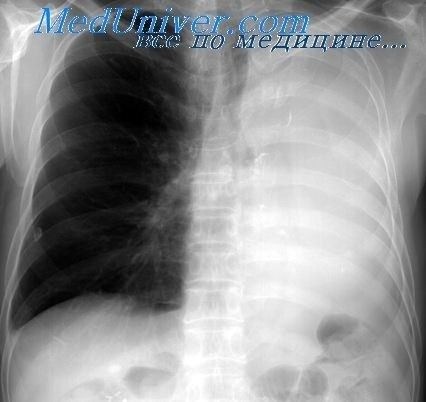

Операция по удалению доли легкого, или лобэктомия, начинается с тщательной подготовки пациента. Важно, чтобы врач заранее провел все необходимые диагностические процедуры, такие как томография, чтобы точно определить степень повреждения органа и выбрать оптимальный вид вмешательства. Лобэктомия может быть выполнена как стандартным хирургическим методом, так и с использованием малоинвазивных технологий, что значительно сокращает восстановительный период. Операция проводится под общим наркозом, и в процессе удаления доли легкого хирург удаляет пораженную часть органа, сохраняя остальные его функции.

Каждый вид резекции легкого требует предварительной тщательной диагностики с использованием методов, таких как томография, для оценки состояния легких. В зависимости от состояния пациента и возраста, а также наличия противопоказаний, врач определяет, какой именно тип вмешательства подходит в конкретном случае. Часто при частичной резекции удаляется только пораженная доля легкого, что позволяет сохранить нормальную функцию органа. Резекция может быть выполнена как с традиционным разрезом, так и с использованием более щадящих малоинвазивных методов, что уменьшает период восстановления и минимизирует последствия операции.